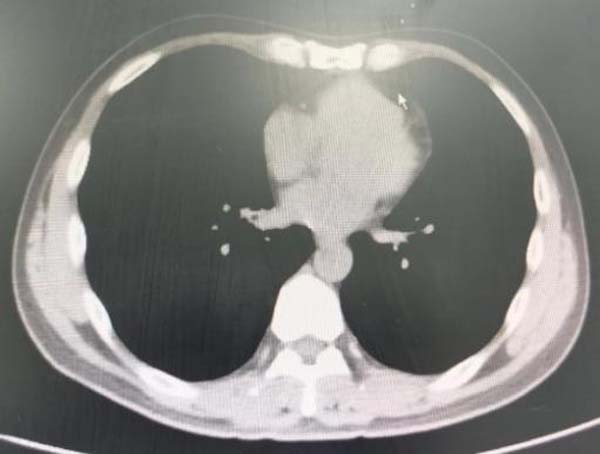

图1.胸部CT显示右肺下叶内基底段支气管结石影

周云芝带领团队反复阅读片子,认真分析结石位置与周围血管的关系,设计了取石方案,制定术中风险预案,同时在术前对陈先生进行了耐心的病情沟通及详细的手术讲解,给予了陈先生莫大的勇气及信心。

图3.胸部CT显示右肺下叶内基底段支气管结石影已消失

为检验手术效果,一周后,患者来到医院复查,胸部CT显示:气道内的石头消失得无影无踪。为表达救命之恩,患者特意送来一面锦旗,感激周云芝主任团队的高超医术及大医精神。